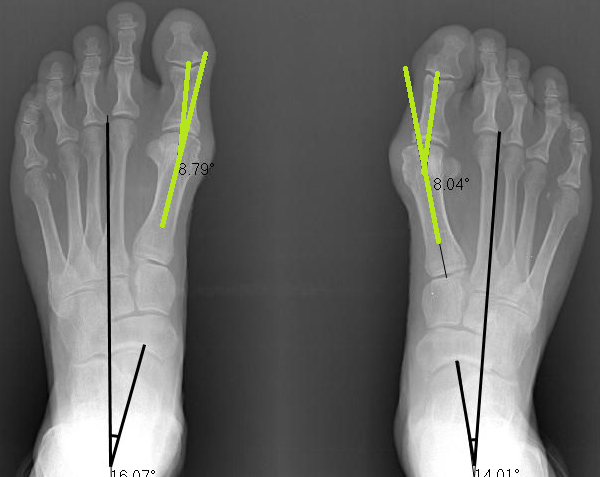

Below is a before and after x-ray. As you can see, her bunions were 26 and 29 degrees misaligned which is moderate-advanced stage bunions.

After a short 3 month course of treatment, we followed up with another x-ray. You can clearly see that her bunions have significantly straightened to 9 and 18 degrees.

17 degrees of straightening without surgery is a fantastic achievement!